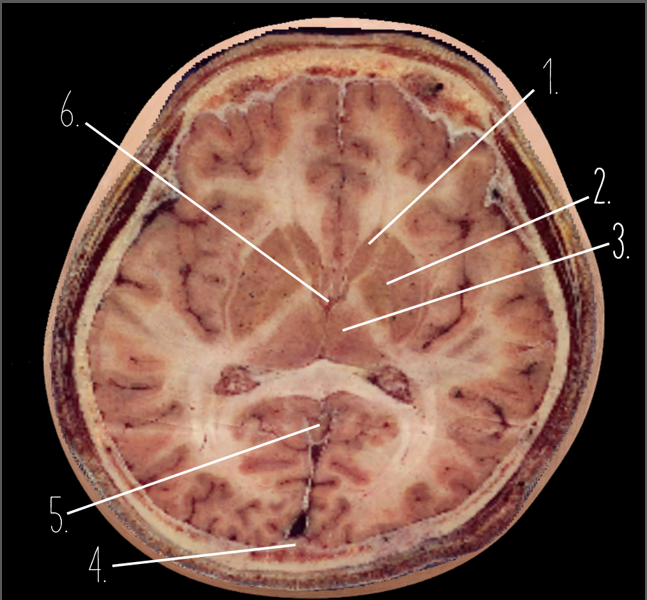

1

Frontal Bone

2

Frontal Lobe

3?

Falx Cerebri

4?

Gray Matter

5?

White Matter

6?

Sulcus